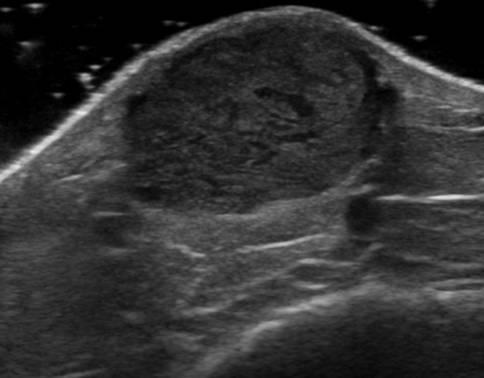

U máu

U máu - Ảnh 4

» Thông tin: Nam giới – 66 tuổi.

» Lâm sàng: Sưng cẳng chân.